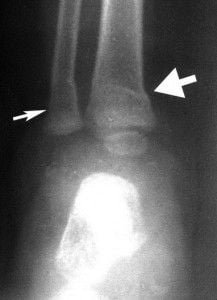

Fragmentación metafisaria presente como fracturas bilaterales.

Fractura pequeña de esquina en la izquierda involucro a la derecha.